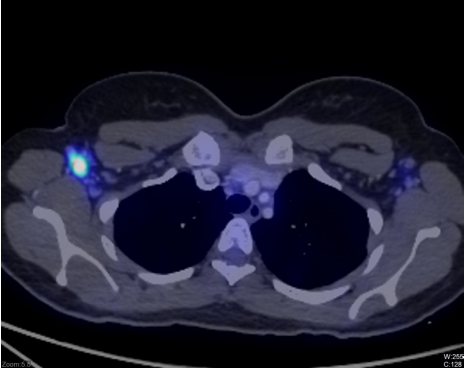

18F-FDG PET-CT Imaging: Metabolically active bilateral cervical nodes (right level II: 18 × 10 mm, SUV_max 11.2), bilateral axillary nodes (right: 21 × 10 mm, SUV_max 12.2—highest metabolic activity), mediastinal nodes (right paratracheal: 14 × 10 mm, SUV_max 4.1), and bilateral external iliac nodes (16 × 7 mm, SUV_max 6.2). No hepatosplenomegaly or pulmonary involvement.

Figure 1: 18F-FDG PET CT scan showing right axillary lymph node.

The high metabolic burden (SUV_max 12.2) exceeded typical KFD ranges (mean 4.2 ± 2.2) but aligns with severity criteria (Seong et al., 2021: SUV_max >9.27 indicates severe disease). This patient's presentation thus represents severe KFD with multisite involvement and heightened inflammatory response, potentially explaining the prominence of monocytosis.